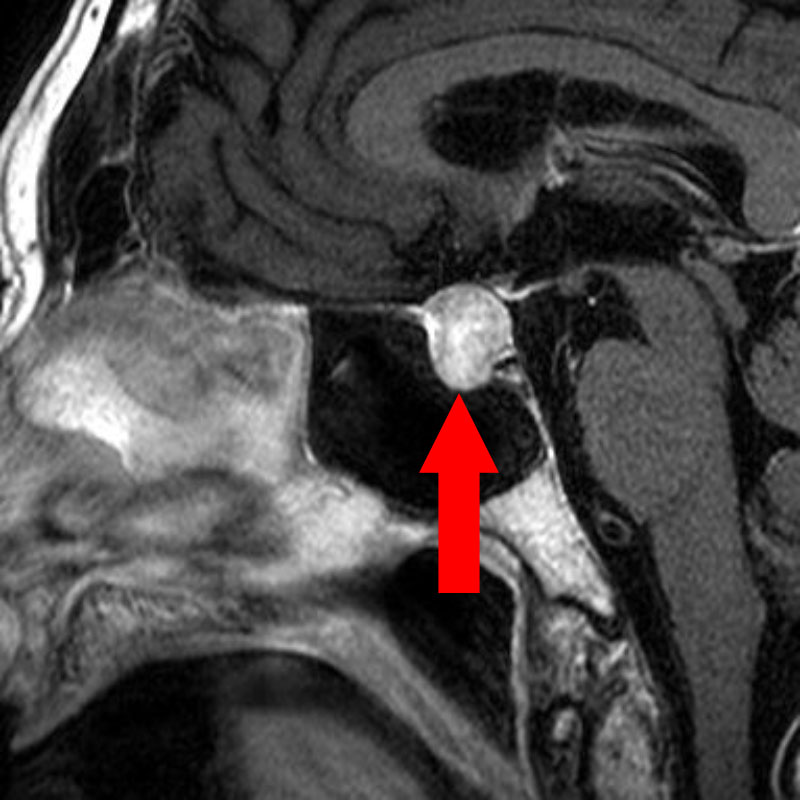

458

'23年9月

70代

鞍上部くも膜のう胞

頭蓋内腫瘍摘出術

No.’23_92 手術前1

No.’23_92 手術前2